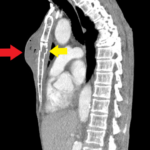

This case report highlights an uncommon sequelae of chest wall trauma that should be evaluated for patients presenting with similar history and symptoms. A 60-year-old man presented to the emergency department (ED) with swelling, fever, and chest wall pain two days after an assault with blunt chest wall trauma. On exam, there was a suspected chest wall abscess, verified on computed tomography (CT) with associated displaced midsternal fracture. This patient was admitted for abscess incision and drainage. While uncommon, chest wall abscess formation is an important condition that should be considered as a differential diagnosis in any patient presenting with chest wall pain post blunt trauma. With few reported similar presentations in the literature, this case is an important addition in a likely underreported phenomenon that requires prompt evaluation and treatment.